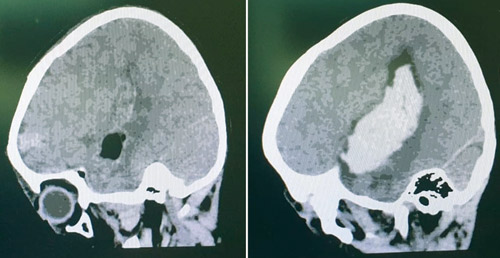

وقال د. ناجي مسعود استشاري جراحة المخ والأعصاب، رئيس الفريق الطبي المعالج، إن الطفل جاء محولاً من أحد المستشفيات إلى الطوارئ، وهو على أجهزة التنفس الصناعي وفي حالة غيبوبة كاملة، ويعاني من توسع في حلقة العين اليسرى، وبمجرد وصوله للمستشفى أخضع لفحوصات دقيقة عدة من بينها التصوير الإشعاعي، الذي أظهر إصابته بمرض «التشوه الشرياني الوريدي الدماغي» النادر، مسبباً له نزيفاً حاداً بالفص الأيسر من المخ، إثر ذلك تدارس الفريق الطبي ملف الطفل على ضوء المعطيات التي وفرتها نتائج التشخيص، وأجمع الفريق الطبي على أن السبيل الأمثل لإنقاذه هو التدخل الجراحي على الفور.

وأضاف د. ناجي أنه تم شرح الخطة العلاجية لوالدي الطفل، ومن ثم أجريت له جراحة ناجحة استغرقت سبع ساعات تم خلالها استئصال التشوهات وسحب النزيف. ومكث الطفل في العناية المركزة لأيام عدة، محاطاً بالرعاية والاهتمام اللازم إلى أن بدأت حالته في التحسن التدريجي واستعاد وعيه وأصبح قادراً على تحريك أطرافه، وبعدها نقل لقسم التنويم وظل تحت المراقبة لمدة أسبوع، حتى استعاد كامل قدراته الذهنية والبدنية بنسبة «99 %»، إذ تخلص من كل الأعراض السابق ذكرها، وهذا ما أكدته صور الأشعة. وبعد أيام عدة خرج من المستشفى -ولله الحمد- بعد أن تحسنت حالته الصحية تماماً.